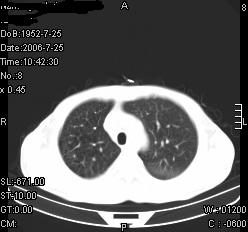

患者,男,54岁,咳嗦,咳痰20天。抗炎治疗2周。现esr76mm/h,目前患者症状明显好转,但发现两次ct片未见明显变化。两次分别做与7.25、7.31。第一次诊断右肺上叶炎症累计胸膜。大家看,从影像上内排除结核吗?

结核的可能性非常大,右上肺病变应该考虑干酪性肺炎。理由:

3.虽经抗炎治疗肺窗病灶有所吸收、减小,但纵隔窗病灶形态、密度、范围无明显变化。如果是单纯的大叶性肺炎,“抗炎治疗2周,目前患者症状明显好转”病灶应该基本消散了,至少也处于吸收消散期,密度变淡、范围变小。同时本病例所示其内的密度不均匀,见多发大小不一空洞样影也不符合大叶性肺炎吸收消散期表现。

病灶特点:片状 索条 结节混杂影,部分融合,密度不均,广泛累及相应胸膜.

临床治疗;二周未吸收.但症状好转.

多考虑:肺结核.